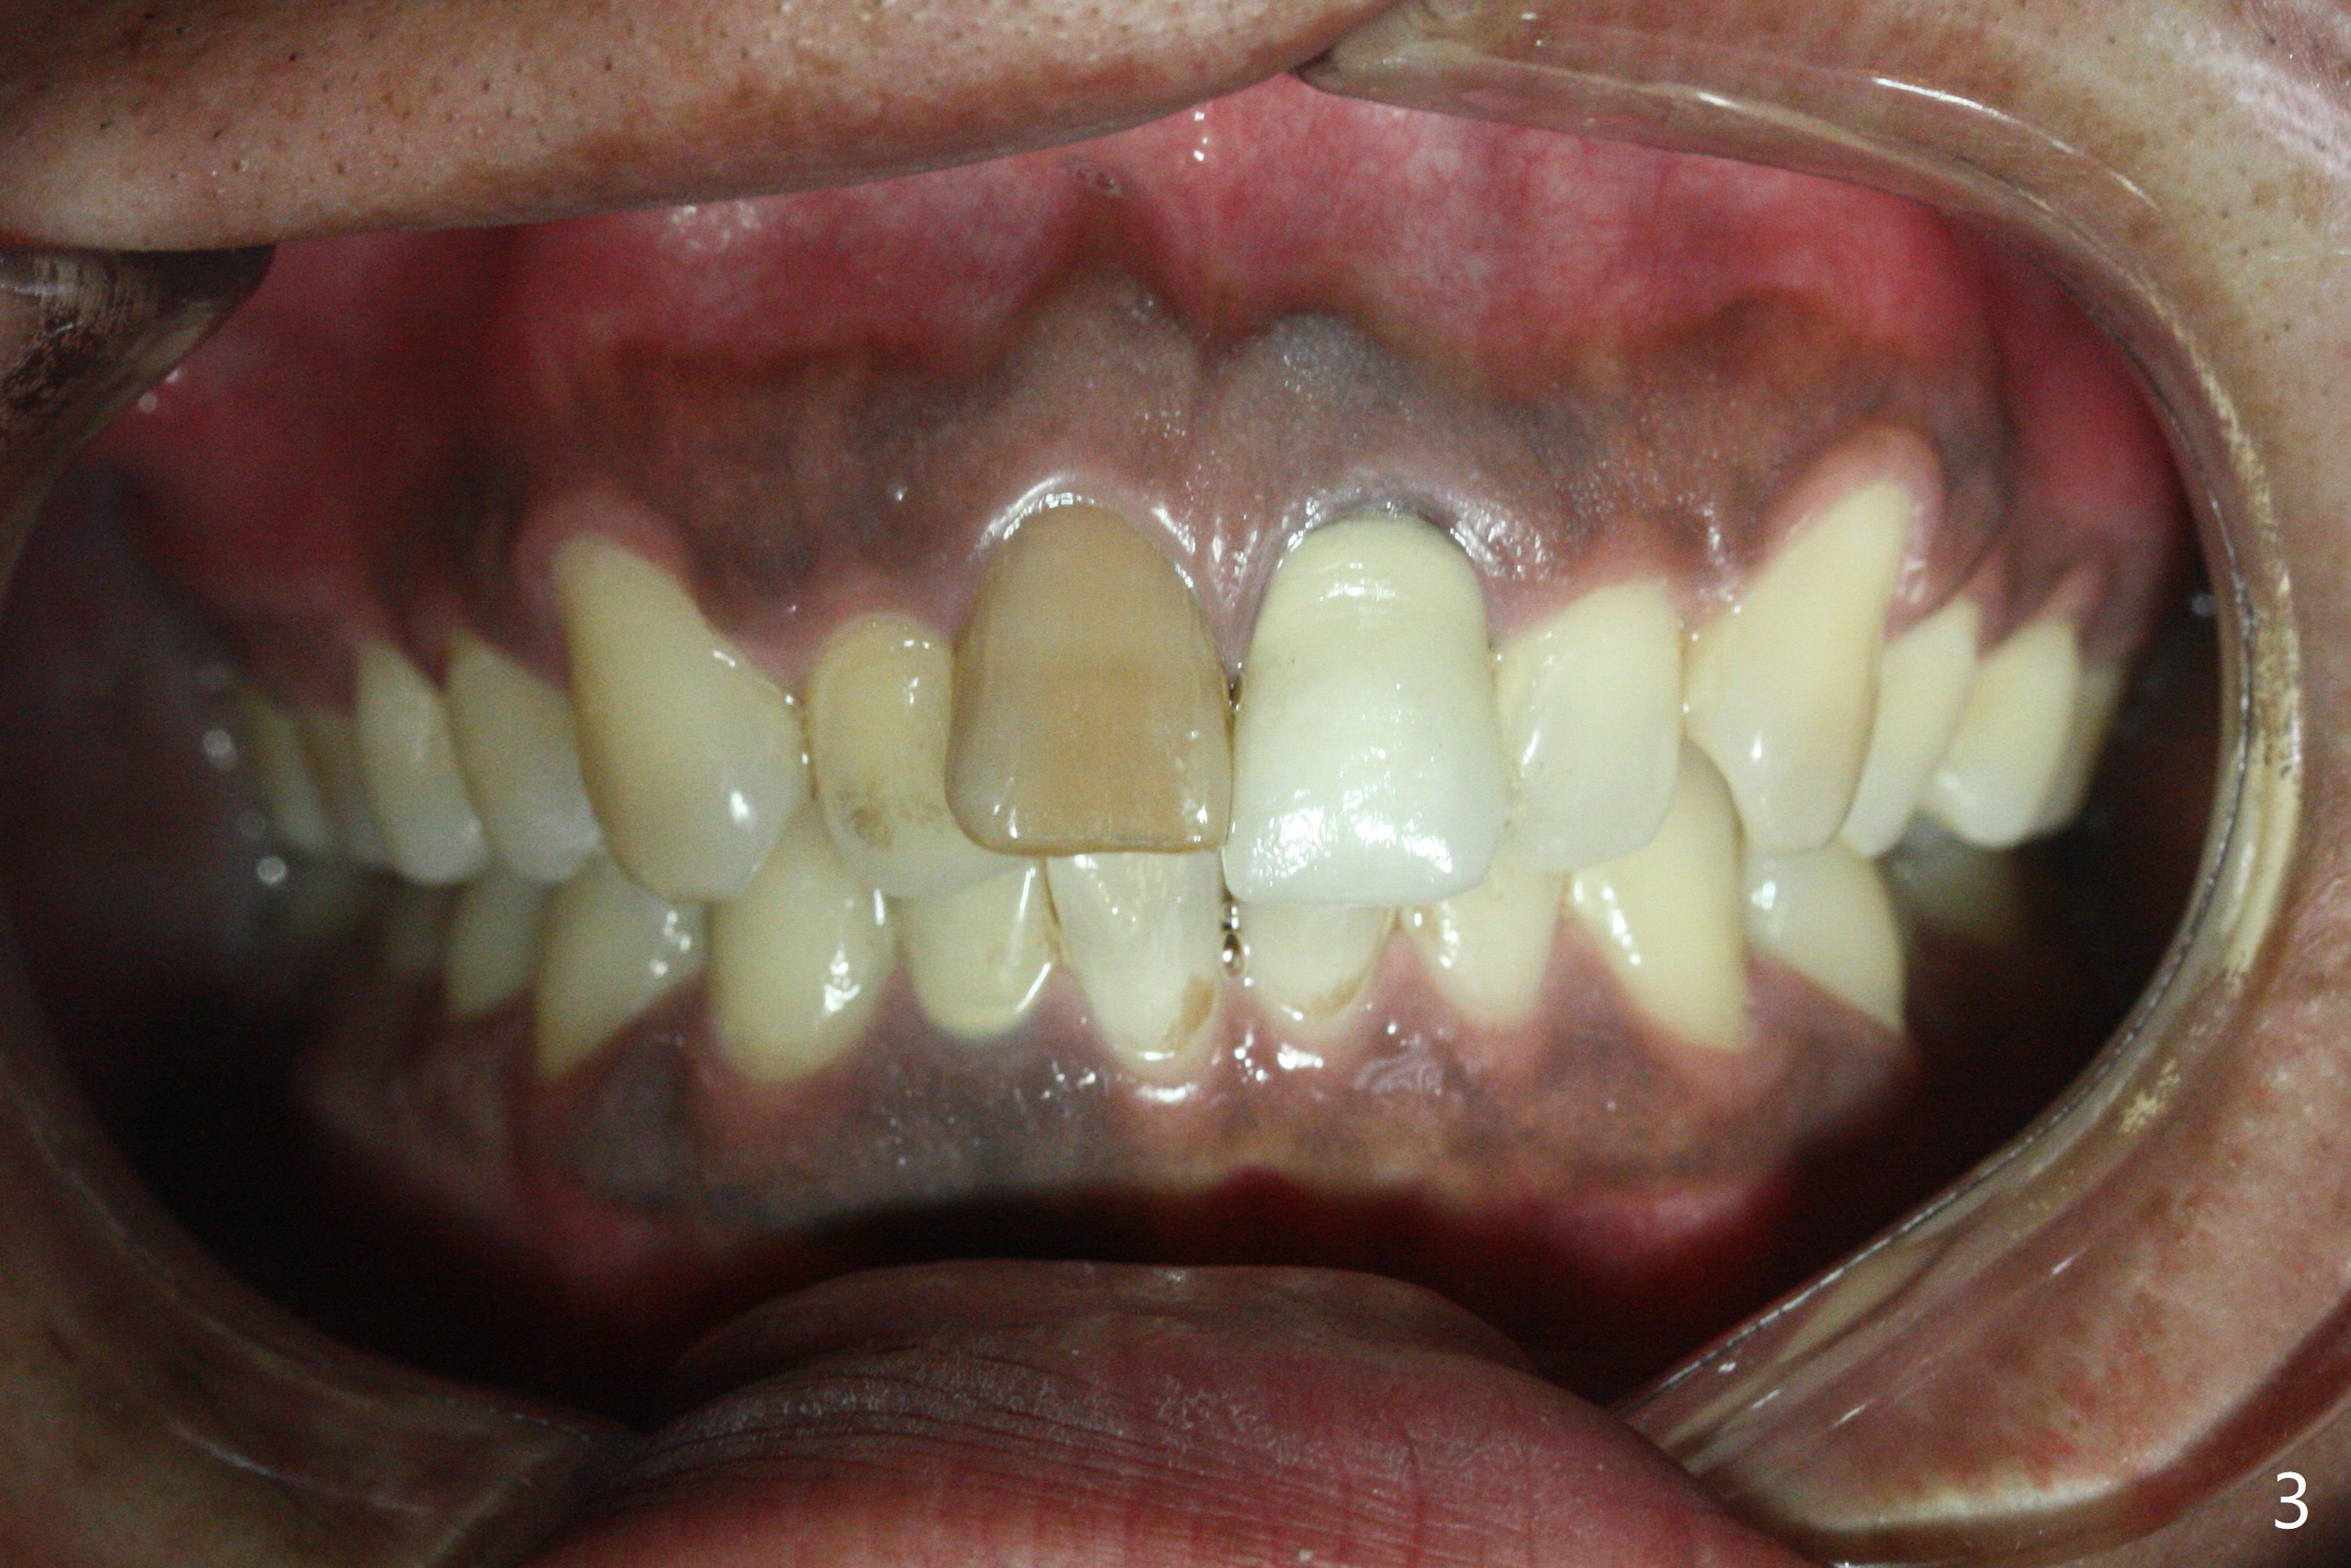

Class II半个牙。这个不用拔牙,Molar distalizaton 和expansion 就可以解决。Oral scan and submit it to Unismile. 建模后。我来帮您设计。张。两个中切牙,位置可以不用排得太完美。排到半程的位置,然后用重做的牙冠来调齐。这样,能减少一些复发的势能。Harry Hu